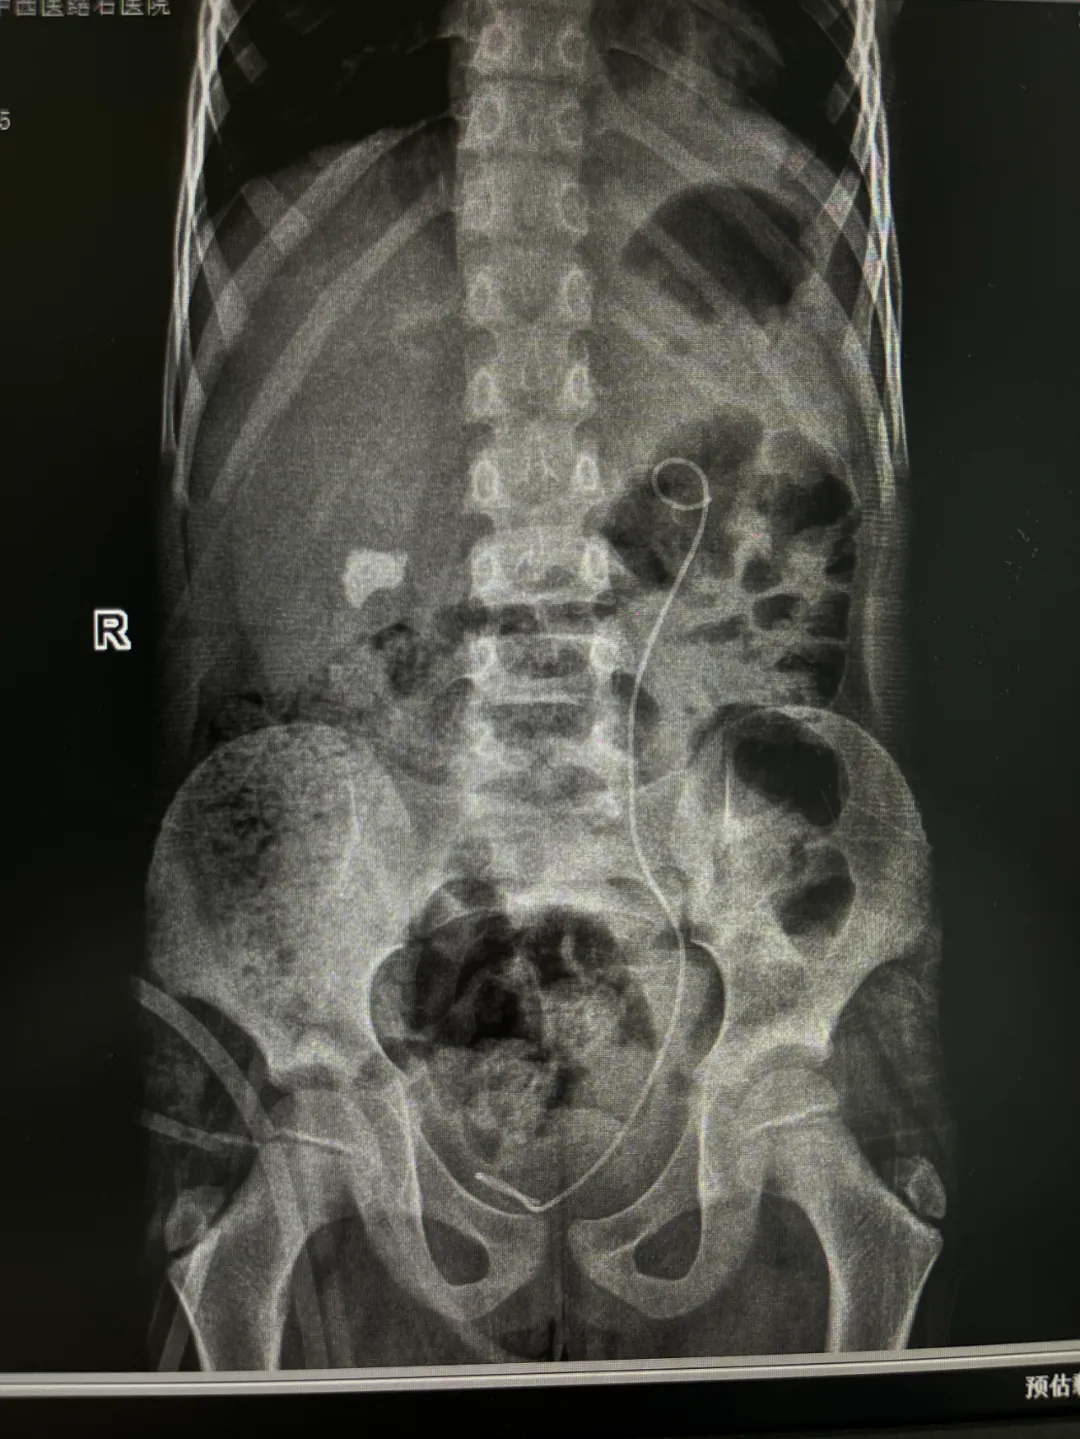

不久前,7 岁的小谢因双肾结石引发肾积水、尿路感染,辗转多家医院后,来我院求得进一步治疗。 两颗大结石,形成了梗阻! 微创手术化解危机 近日,一名7岁的小患者因“双肾结石并积水和感染”来我院就诊,收住院后,泌尿外科医生结合患者病情制定微创手术(分两期完成)治疗方案。待患儿感染控制后分别在全麻下行微创碎石取石手术,于近日进行了第一期手术,手术过程顺利。 手术由院长亲自指导、泌尿外科医师主刀,采用微创碎石取石术——该微创方式更契合儿童器官娇嫩的生理特点,能减少对身体的干扰,无需腹部切口,仅通过尿道、膀胱进入输尿管,通过微创方式将结石处理后取出,再用取石网篮将碎石取出。 由于儿童输尿管管腔狭窄,手术操作难度更大,外科主任团队凭借多年治疗儿童泌尿系疾病的经验,小心翼翼地操控器械,仅用40分钟就顺利清除了左肾结石,对梗阻问题开展针对性干预,这也为为后续诊疗步骤奠定基础;对于右侧肾内的结石,则是择期进行手术。 ▲一期手术完成后的影像检查 术后小结! “儿童肾结石不像成人那么常见,但一旦发生,若合并梗阻、感染,可能对发育中的肾脏造成不可逆损伤。”主治医师在术后科普中提醒,儿童肾结石多与饮水不足、饮食结构失衡、代谢异常等因素相关,家长日常要注意让孩子多喝白开水(每日饮水量建议 1500-2000ml),少喝含糖饮料,避免过量食用菠菜、巧克力、坚果等草酸含量高的食物,定期体检时可关注泌尿系超声检查,做到早发现、早干预。 此次为小谢成功诊疗,是我院儿科与泌尿外科多学科协作的又一次实践。多年来,我院始终坚持 “以患者为中心”,通过微创手术、个体化方案,长期为低龄患儿的结石、梗阻等泌尿系问题提供诊疗服务,用精准医疗守护儿童泌尿健康,始终以 “患儿为中心” 优化诊疗服务流程。未来,我院将持续提升儿童专科诊疗能力,为更多患病儿童筑起健康屏障。

▲影像检查显示:小谢双侧输尿管内竟卡着